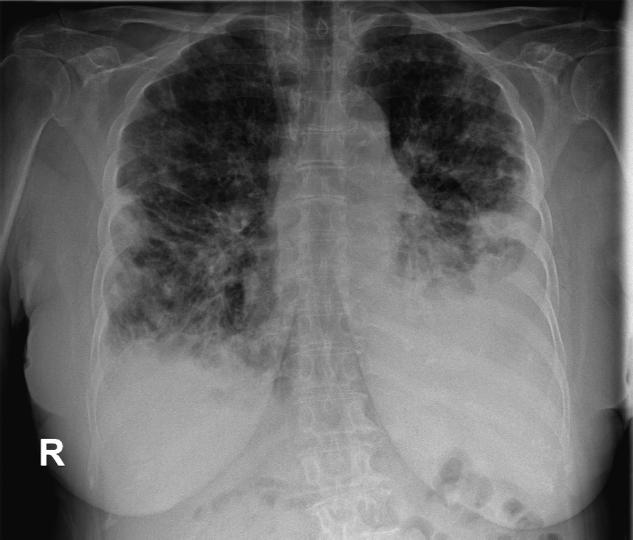

Chest X-ray at first discharge. Slow resolution of opacities with residual left pleural effusion.

While admitted to the Pneumology Department, repeated diagnostic and therapeutic thoracenteses were performed, with subsequent bacteriological, fungal, biochemical, cytological and bacillary analysis of the pleural fluid. As the initial results were non-specific, the hypothesis of infectious pathology was maintained. Cytological examination showed a reactive inflammatory effusion; bacteriological and fungal cultures were negative, as was mycobacteriological testing. The patient received intravenous therapy with double antibiotics (third-generation cephalosporin and third-generation fluoroquinolone), antifungal (fluconazole), probiotics, vitamins and supplemental oxygen. Initial progression was slowly favourable, with moderate clinical improvement, but latent respiratory insufficiency persisted, as demonstrated by the 6-min walk test (6MWT), and radiologic changes resolved slowly (Figure 2).